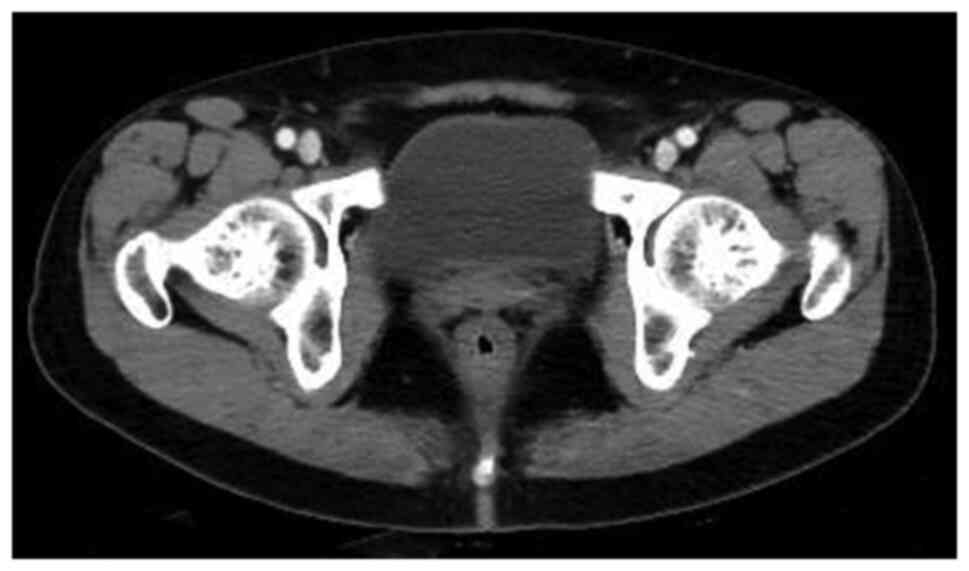

Figure 5

A 47-year-old man with gross hematuria. Coronal computed tomography scan of bladder shows multiple polypoid soft-tissue mass on the superior wall.

The CT findings showed that 8 (89%) patients had one tumor and 1 (11%) patient had multiple tumors. The bladder IMT size ranged from 1.3x2.1 to 4.8x5.1 cm2. Tumors occurred in the posterior wall in 2 (22%) patients, 5 (30%) patients had tumors occurred in the superior wall, 1 (11%) patient had tumors occurred in the front wall, and 1 (11%) patient had tumor occurred in the left wall (Fig. 2, Fig. 3, Fig. 4 and Fig. 5). An endophytic growth pattern (Fig. 3) was identified in 4 (44%) patients, an exophytic growth pattern (Fig. 2) was observed in 2 (22%) patients, and a mixed growth pattern (Fig. 5) was revealed in 3 (33%) patients. The tumor manifests morphologically as either polypoid (n=5), or cauliflower-like (n=1) soft-tissue mass with a wide base in the cavity, or a limited thick-walled (n=3) in the bladder. The tumor margins were smooth (n=8) or lobulated (n=1) and the tumor boundaries were either clear (n=7) or ill-defined (n=2).